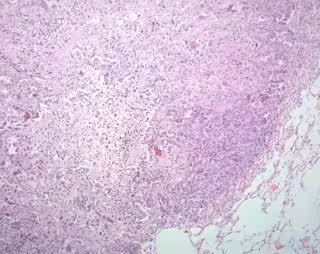

Cáncer de pulmón - CNIO - Archivo